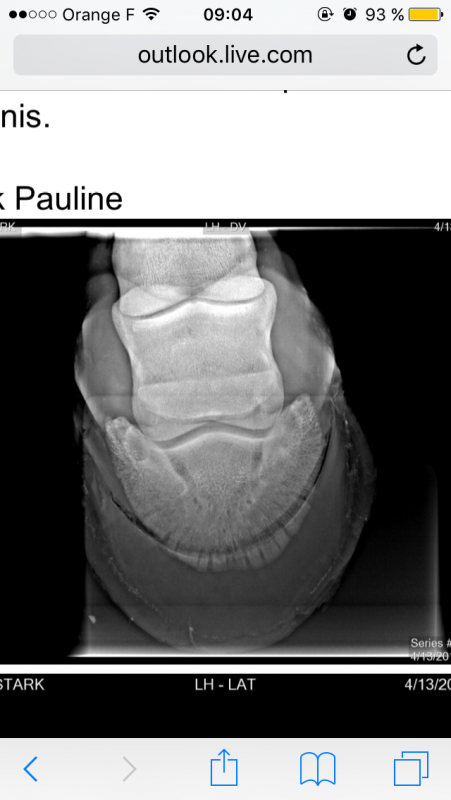

son sabot (on a fait des radios et on a endormi son pied et il boitait plus donc ça venait du pied ). Résultat : un mois de convalescence.

Ben il s'auto flagelle ce maréchal....Cette ligne visible est ancienne , elle date pas d'hier et ce sabot est trop noyé sous l'huile !geriko42 - le 18/05/2017 à 06h49

Regarde bien le deuxième pied, c'est pas aussi flagrant mais il a aussi une légère ligne, au même niveau.paulines - le 18/05/2017 à 09h02

Je vois également la ligne c'est vrai, cela fait 3 ans que j'ai mon cheval et avec moi il n'a eu aucun soucis de fourbure. Il n'a eu que deux propriétaires différents (son éleveuse et moi), elle l'a eu jusqu'à ses 6 ans et moi je l'ai depuis , elle ne m'a pas informé qu'il était sujet aux fourbures ou quoique ce soit .expar - le 18/05/2017 à 10h52 2 j'aime

Ce n'est pas forcément une fourbure, mais un événement. On dit qu'en regardant les sabots d'un cheval, on peut voir tout ce qui s'est passé : changement d'alimentation, condition de vie (box/paddock à pré, par ex.) et autres. Là, les 2 sabots ont cette lignes, à toi de penser à ce qui a bien pu se passer, il y a quelques mois en arrière.paulines - le 18/05/2017 à 12h45